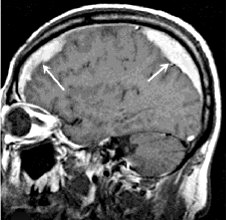

Внутричерепная гипотензия: КТ-исследования и их интерпретация

Раздел: Образы вокруг